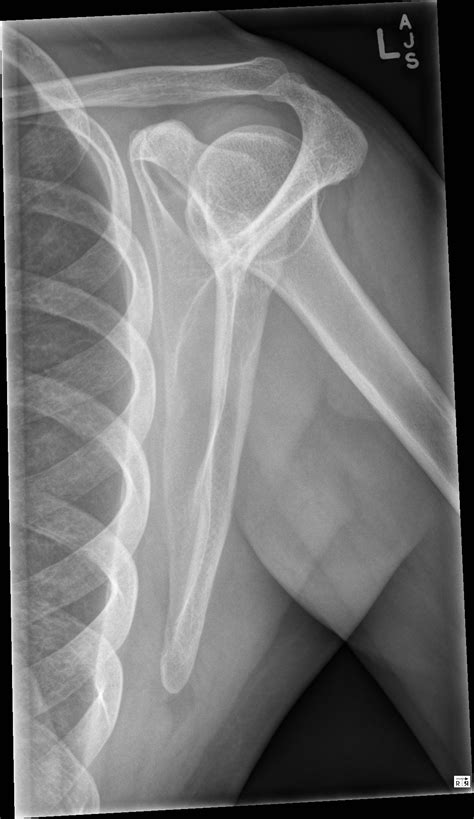

Understanding the significance of a shoulder X-ray normal result is crucial for both medical professionals and patients. A shoulder X-ray is a common diagnostic tool used to evaluate the bones, joints, and surrounding soft tissues of the shoulder. This imaging technique helps identify fractures, dislocations, arthritis, and other abnormalities. However, interpreting a shoulder X-ray normal result requires a thorough understanding of the anatomy and potential pathologies that can affect the shoulder.

The shoulder is a complex joint composed of several bones, muscles, and ligaments. The primary bones involved are the humerus (upper arm bone), scapula (shoulder blade), and clavicle (collarbone). The shoulder joint is a ball-and-socket joint, allowing for a wide range of motion. The rotator cuff, a group of muscles and tendons, plays a crucial role in stabilizing the shoulder and enabling movement.

Interpreting a Shoulder X-Ray Normal Result

When a shoulder X-ray normal result is reported, it means that the X-ray images do not show any visible abnormalities in the bones or joints. This can be reassuring for patients experiencing shoulder pain, as it indicates that there are no obvious fractures or dislocations. However, it is important to note that a normal X-ray does not rule out all possible causes of shoulder pain.